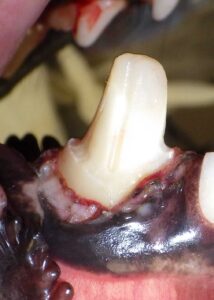

Fractured Tooth With Pulp Exposure

Often caused by chewing bones or trauma, this exposes the nerve and allows infection to enter.

Strategic or Essential Teeth

Key teeth—such as canines or upper premolars—help pets chew, maintain jaw alignment, and carry toys. Preserving them can be more beneficial than extraction.